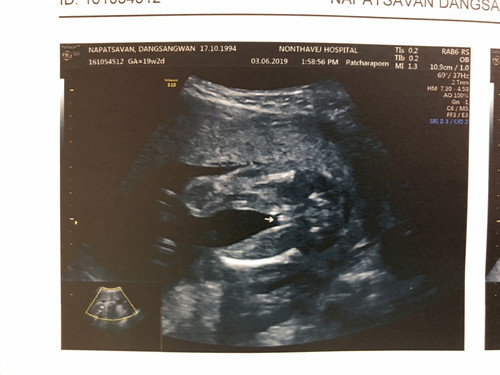

อัลตราซาวด์ตอนท้อง 19 สัปดาห์คุณหมอบอกน่าจะเป็นผู้หญิงเพราะเห็นแคมนี่ท้องที่สามแล้วมีลูกชายมาสองคนแล้วอยากมีลูกสาวมากๆ มีใครเคยผลซาวไม่ตรงบ้างคะ แม่แอบกังวล ?

น่าจะผู้หญิงมั้งคะ ของเราก็ผู้หญิงคะ